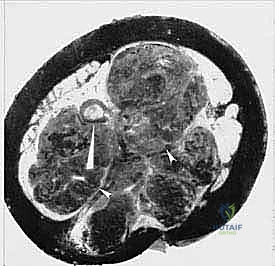

الخطوة الرابعة: قص العظام (Osteotomy) وفصل الحوض

باستخدام مناشير عظمية متقدمة، يتم فصل عظام الحوض عن العمود الفقري (عند المفصل العجزي الحرقفي) وفصلها من الأمام (عند الارتفاق العاني). يتطلب هذا دقة متناهية لضمان استئصال الورم بالكامل دون المساس بالأعضاء الداخلية في الحوض (مثل المثانة والمستقيم).